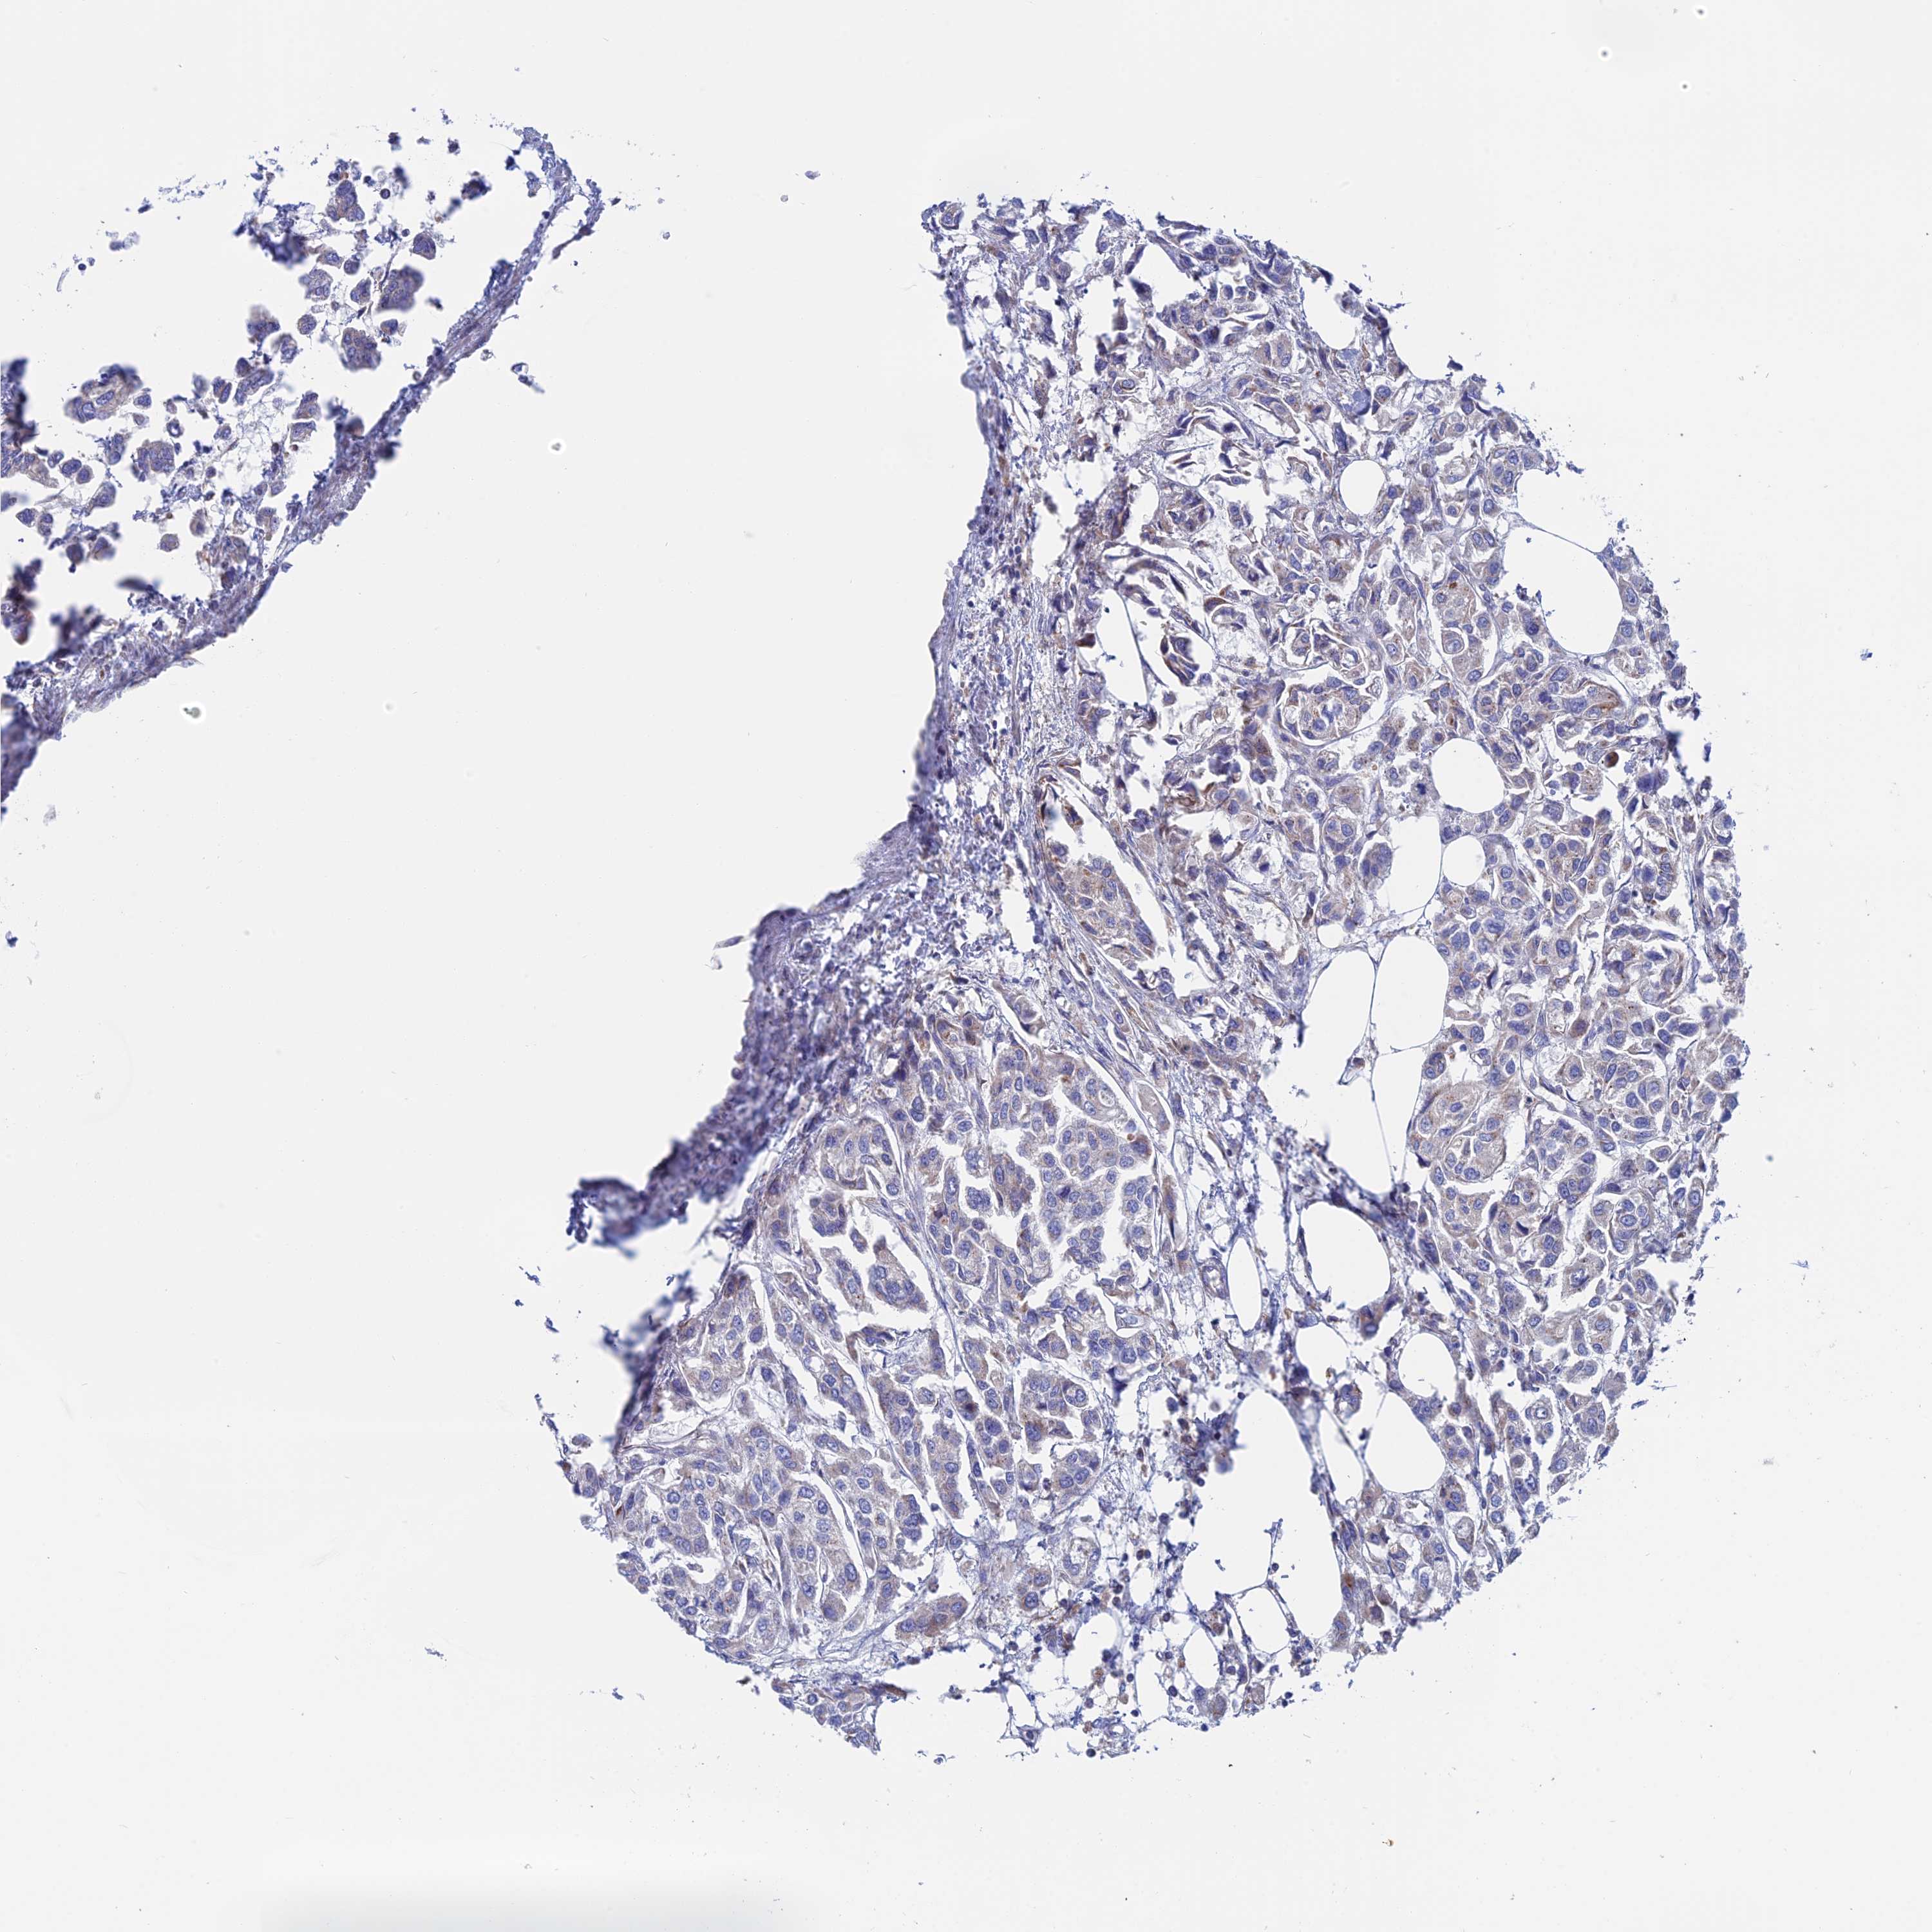

UROTHELIAL CANCER - Protein expressioni

A mouse-over function shows sample information and annotation data. Click on an image to view it in a full screen mode. Samples can be filtered based on level of antibody staining by selecting one or several of the following categories: high, medium, low and not detected. The assay and annotation is described here.

Antibody stainingi

Antibody staining in the annotated cell types in the current human tissue is reported as not detected, low, medium, or high, based on conventional immunohistochemistry profiling in selected tissues. This score is based on the combination of the staining intensity and fraction of stained cells.

Each image is clickable and will lead to virtual microscopy that enables deeper exploration of all samples and also displays staining intensity scores, fraction scores and subcellular localization as well as patient and tissue information for each sample.

Antibody HPA042629

Antibody HPA042838

Urothelial carcinoma, High grade

Urothelial carcinoma, Low grade